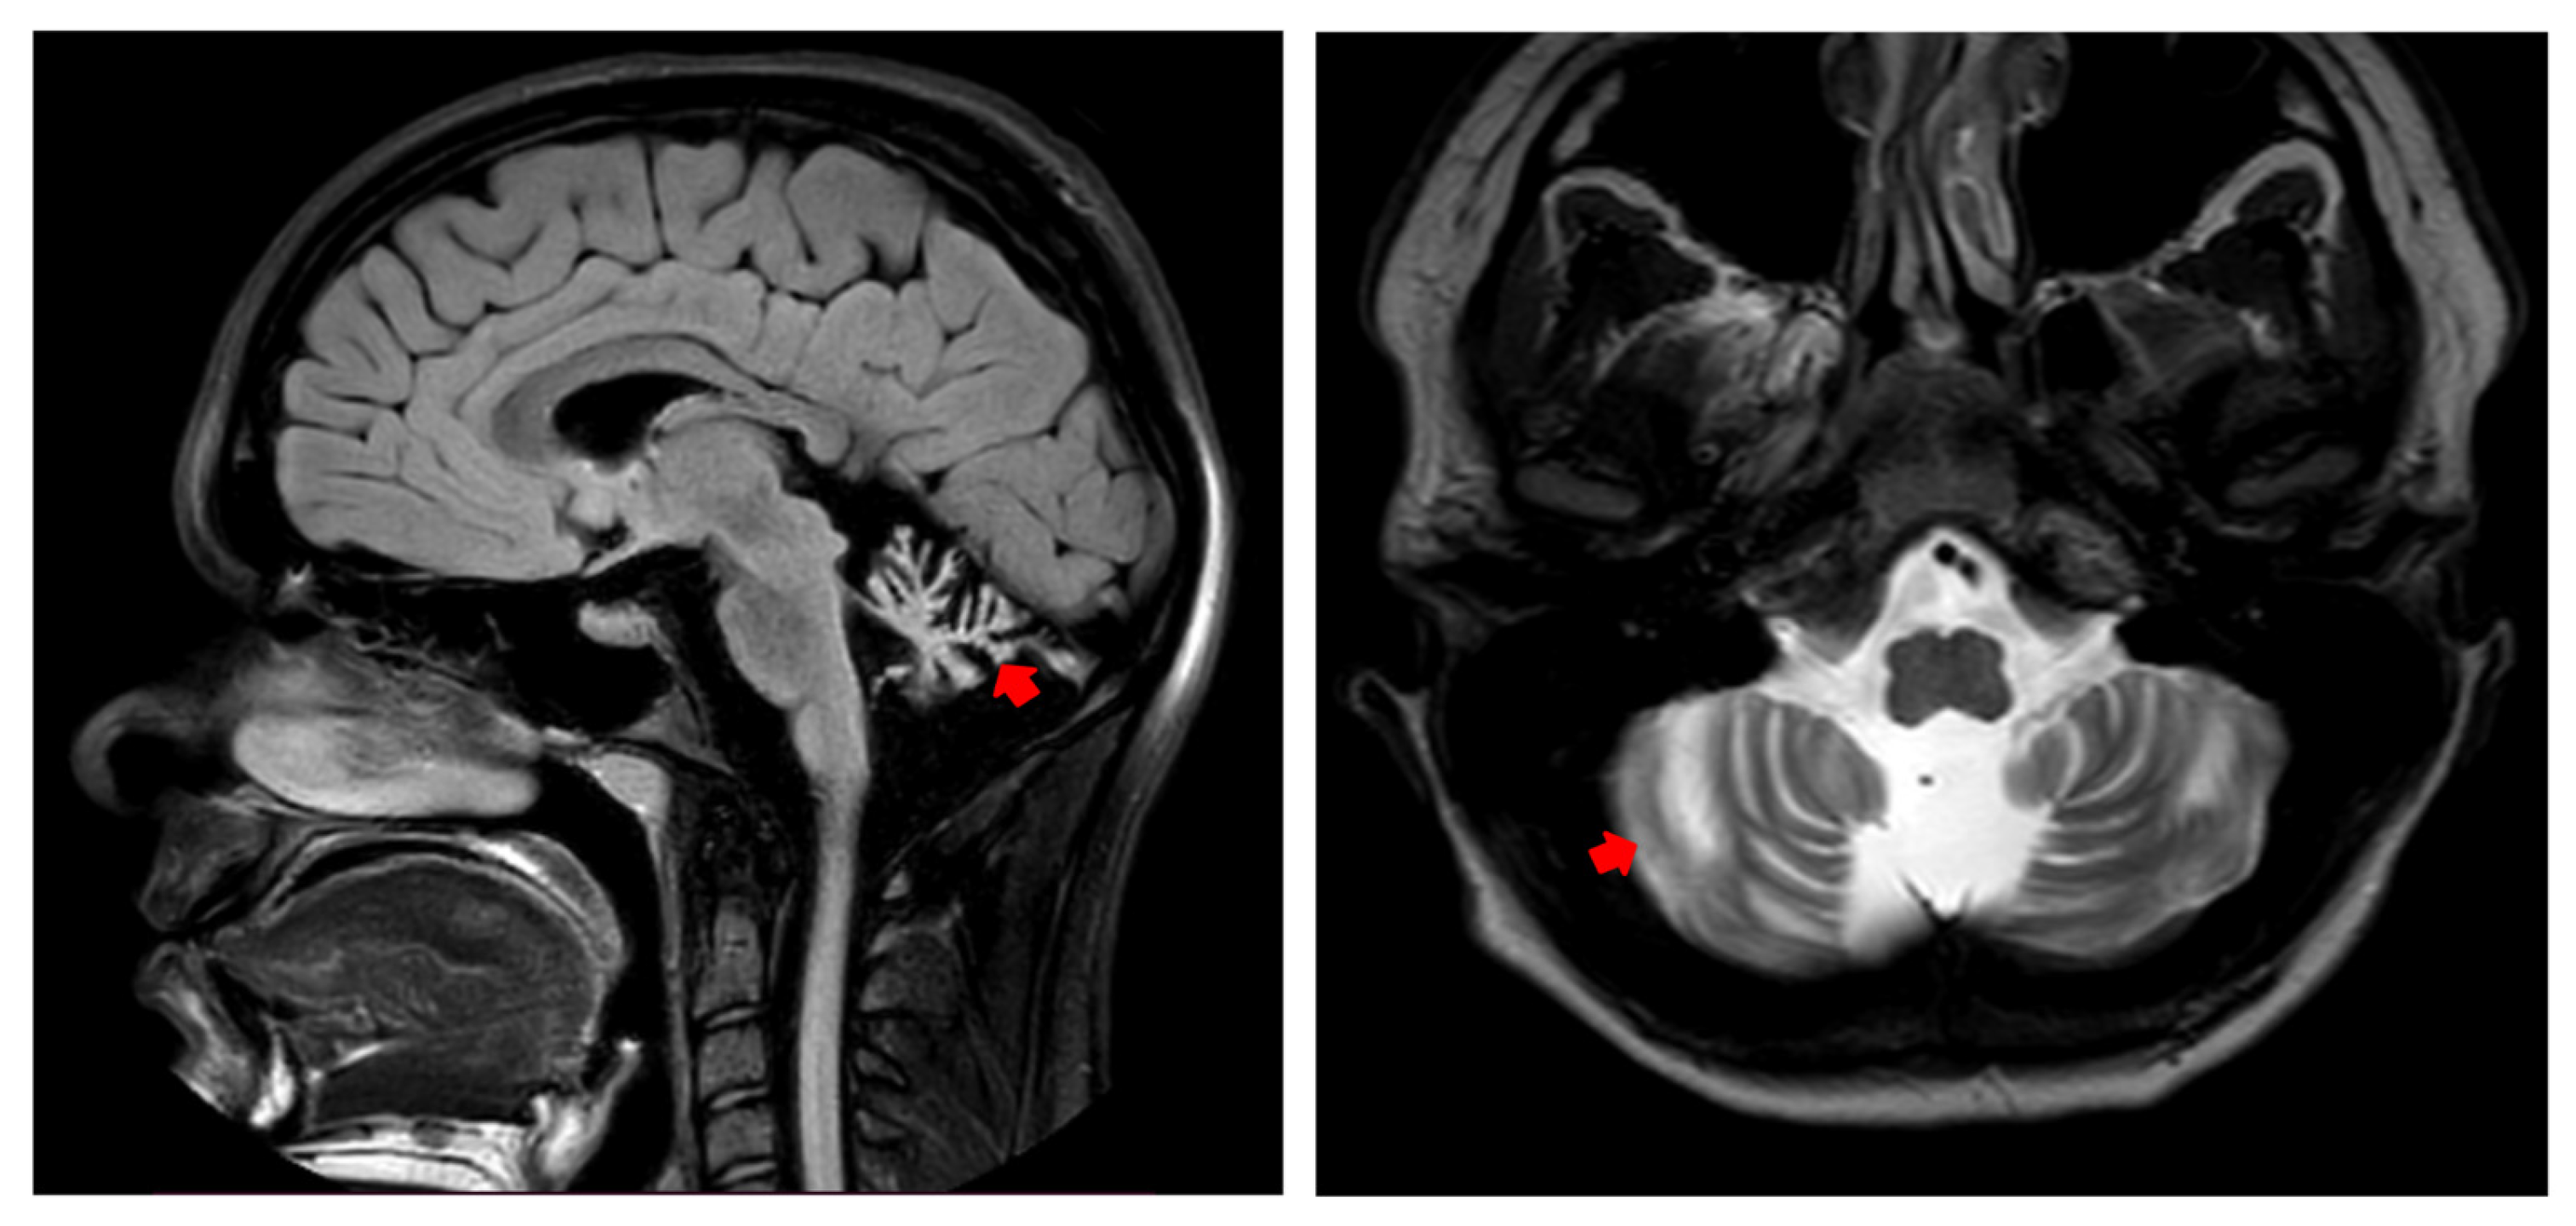

3.2.3. Evaluation at 17 Years Old